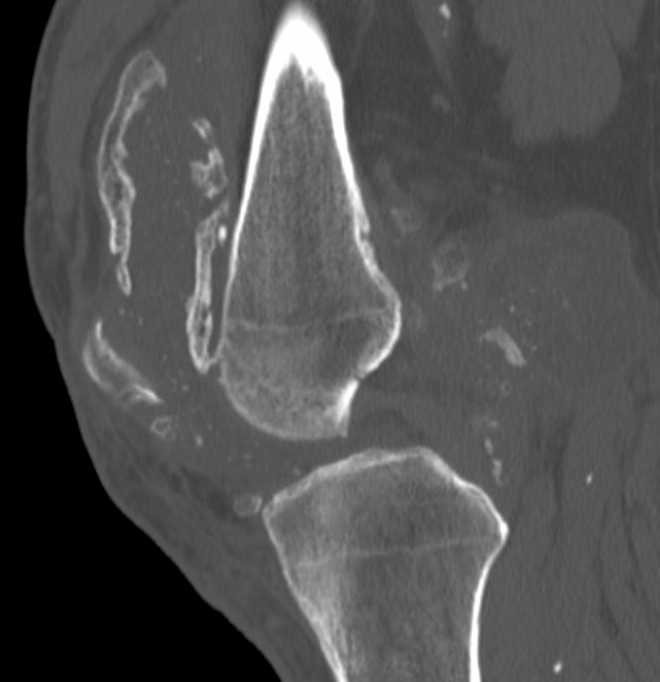

CT

Demonstrate osseous / calcified bodies